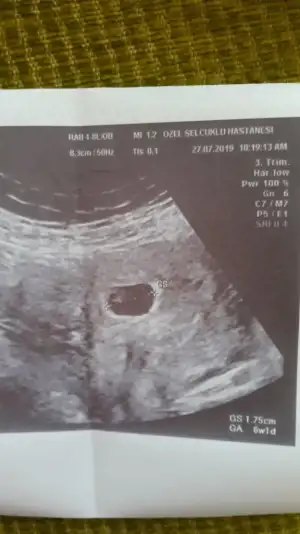

Günaydın kizlar bugun ilk dr kontrolum vardi. Dr bebegi gördü kalp atisi icin 1 hafta sonra cagirdi. Cuma tekrar gidecegim insallah hayirlisiyla duyarim.Rabbim tez zamanda sizlerede nasip etsin :dua: :dua: :dua:

• 20190727_095606.webp

20190727_095606.webp

24,4 KB · Görüntüleme: 61